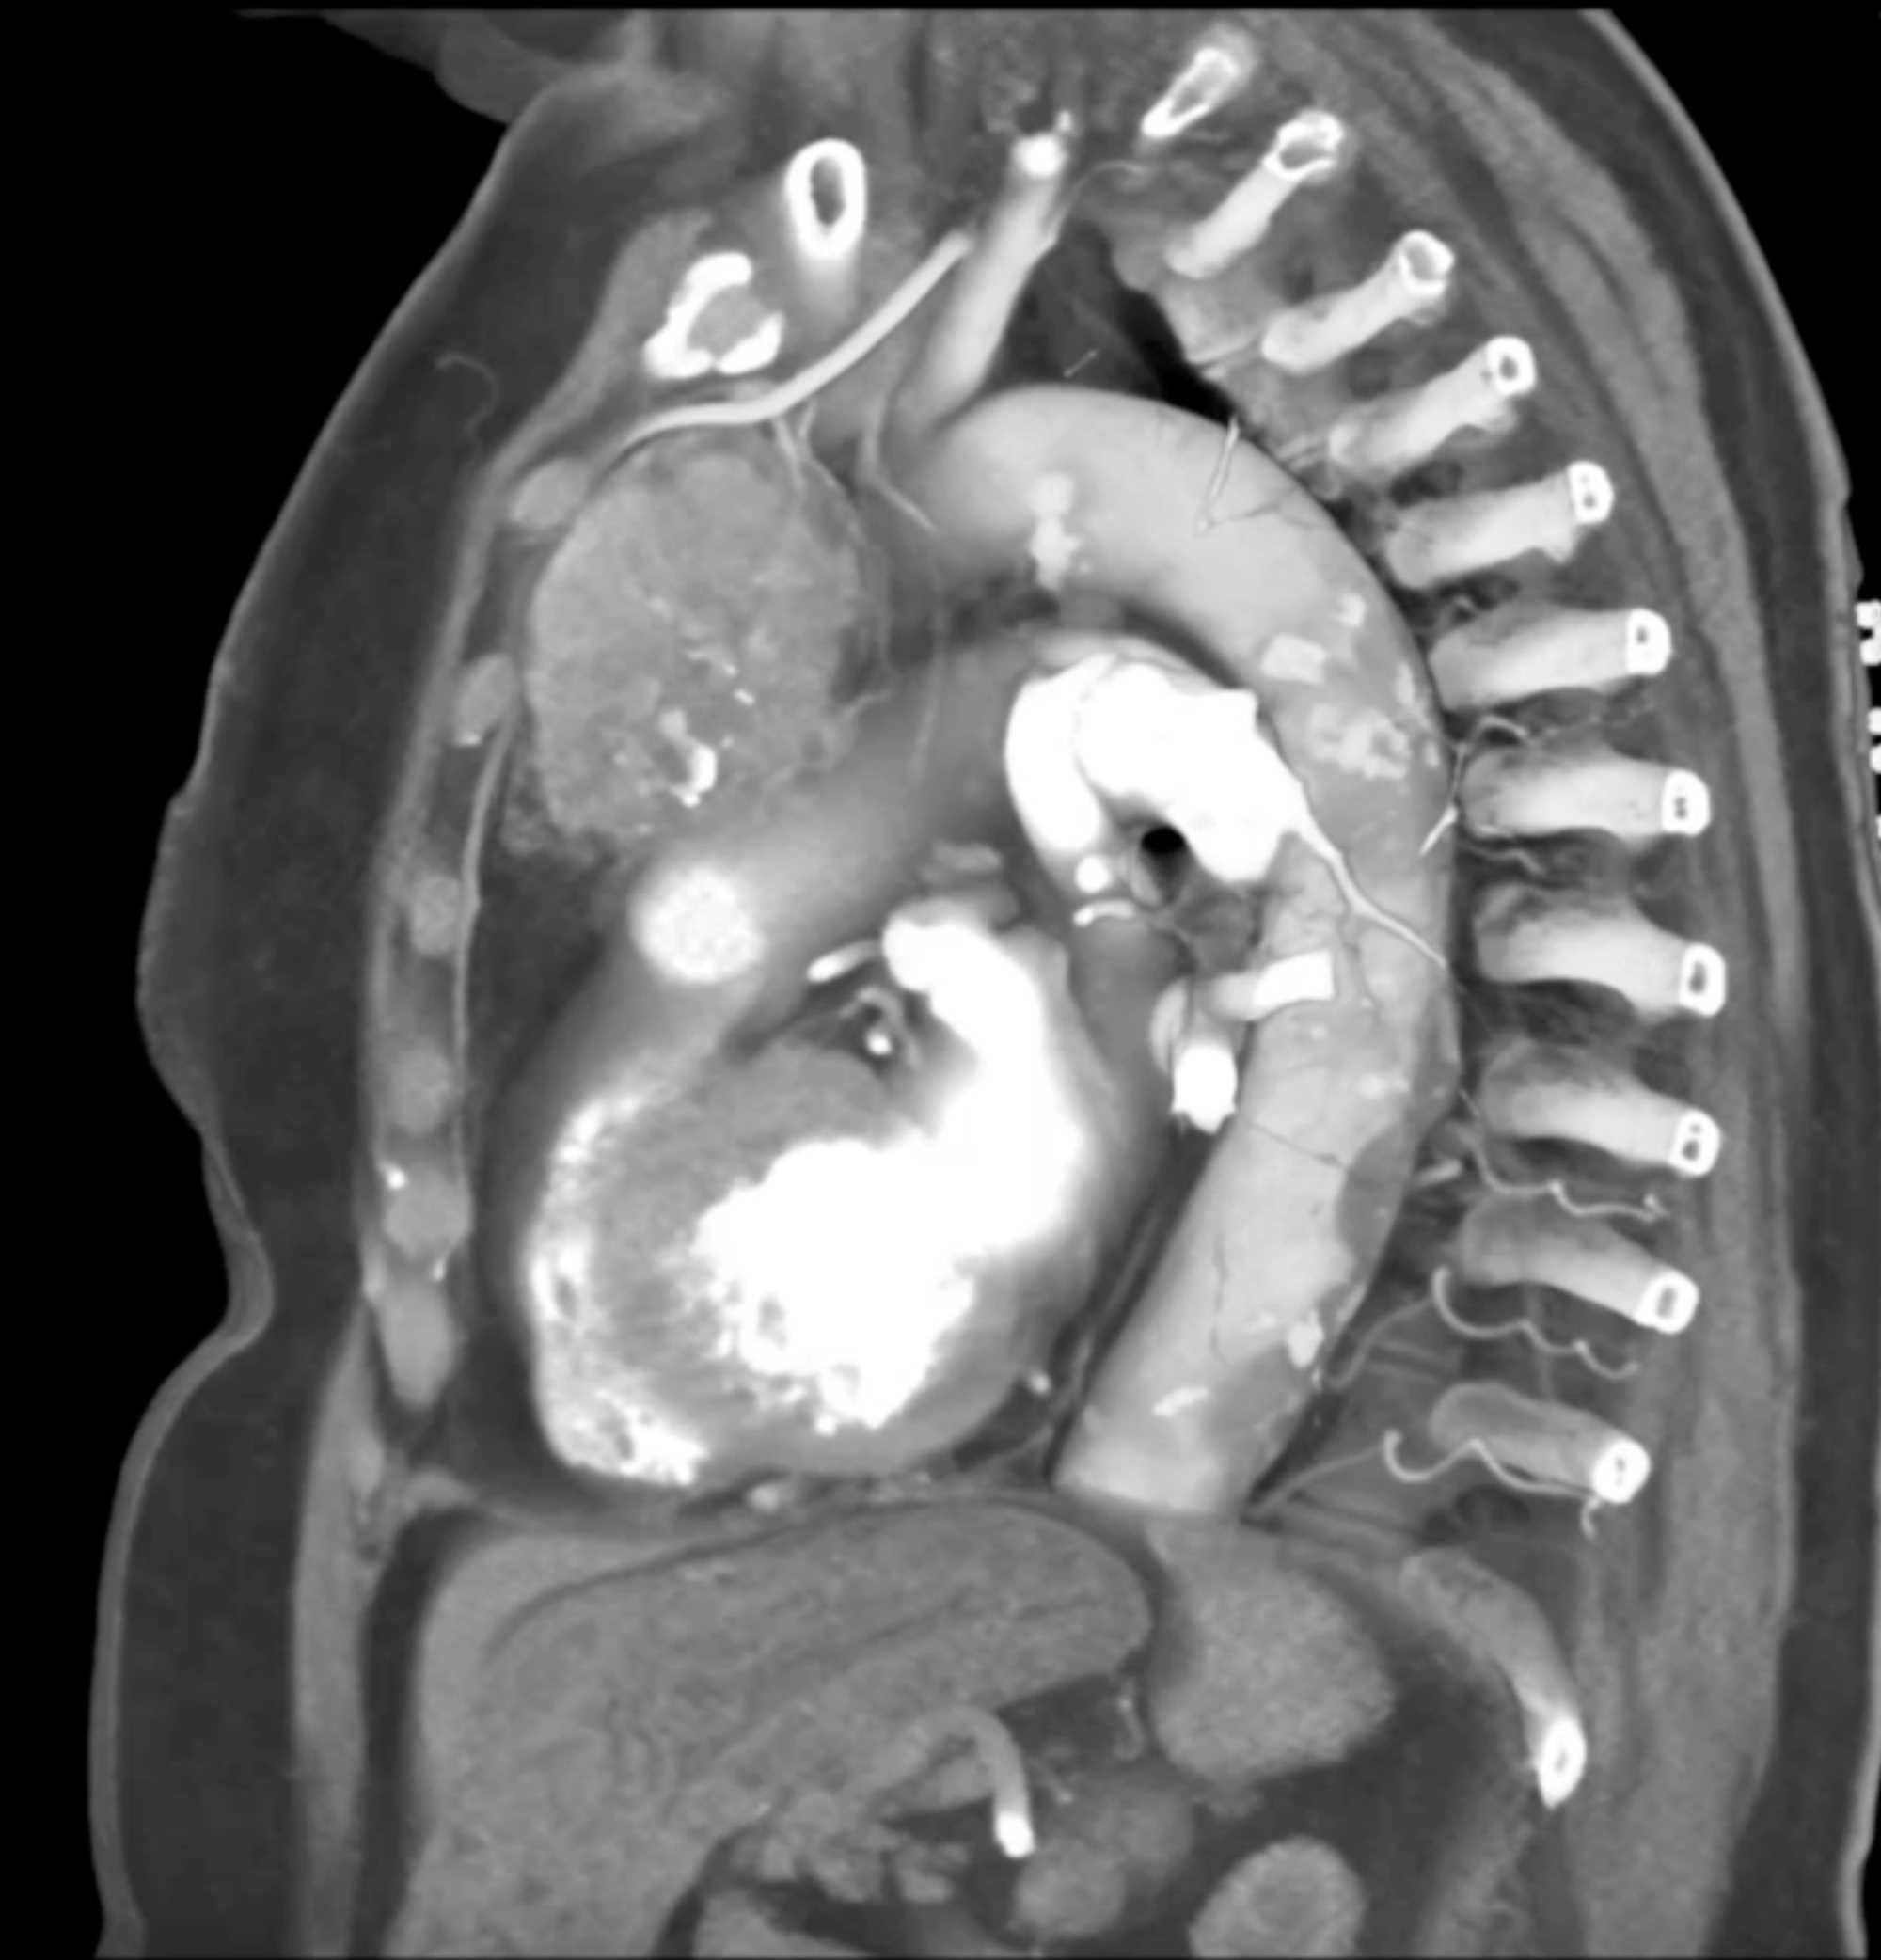

Thymic Carcinoma